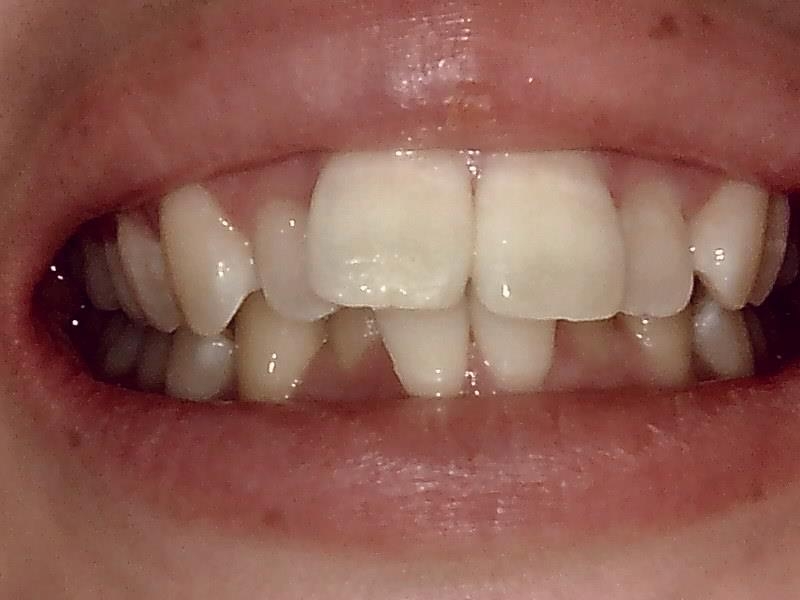

術後の口腔内写真 正面観

スマイルラインも美しくなり、前突した歯も改善され噛み合わせもしっかり正常に戻しました。

治療期間も短く、患者様も治療を頑張って下さったので綺麗に歯が並びました。